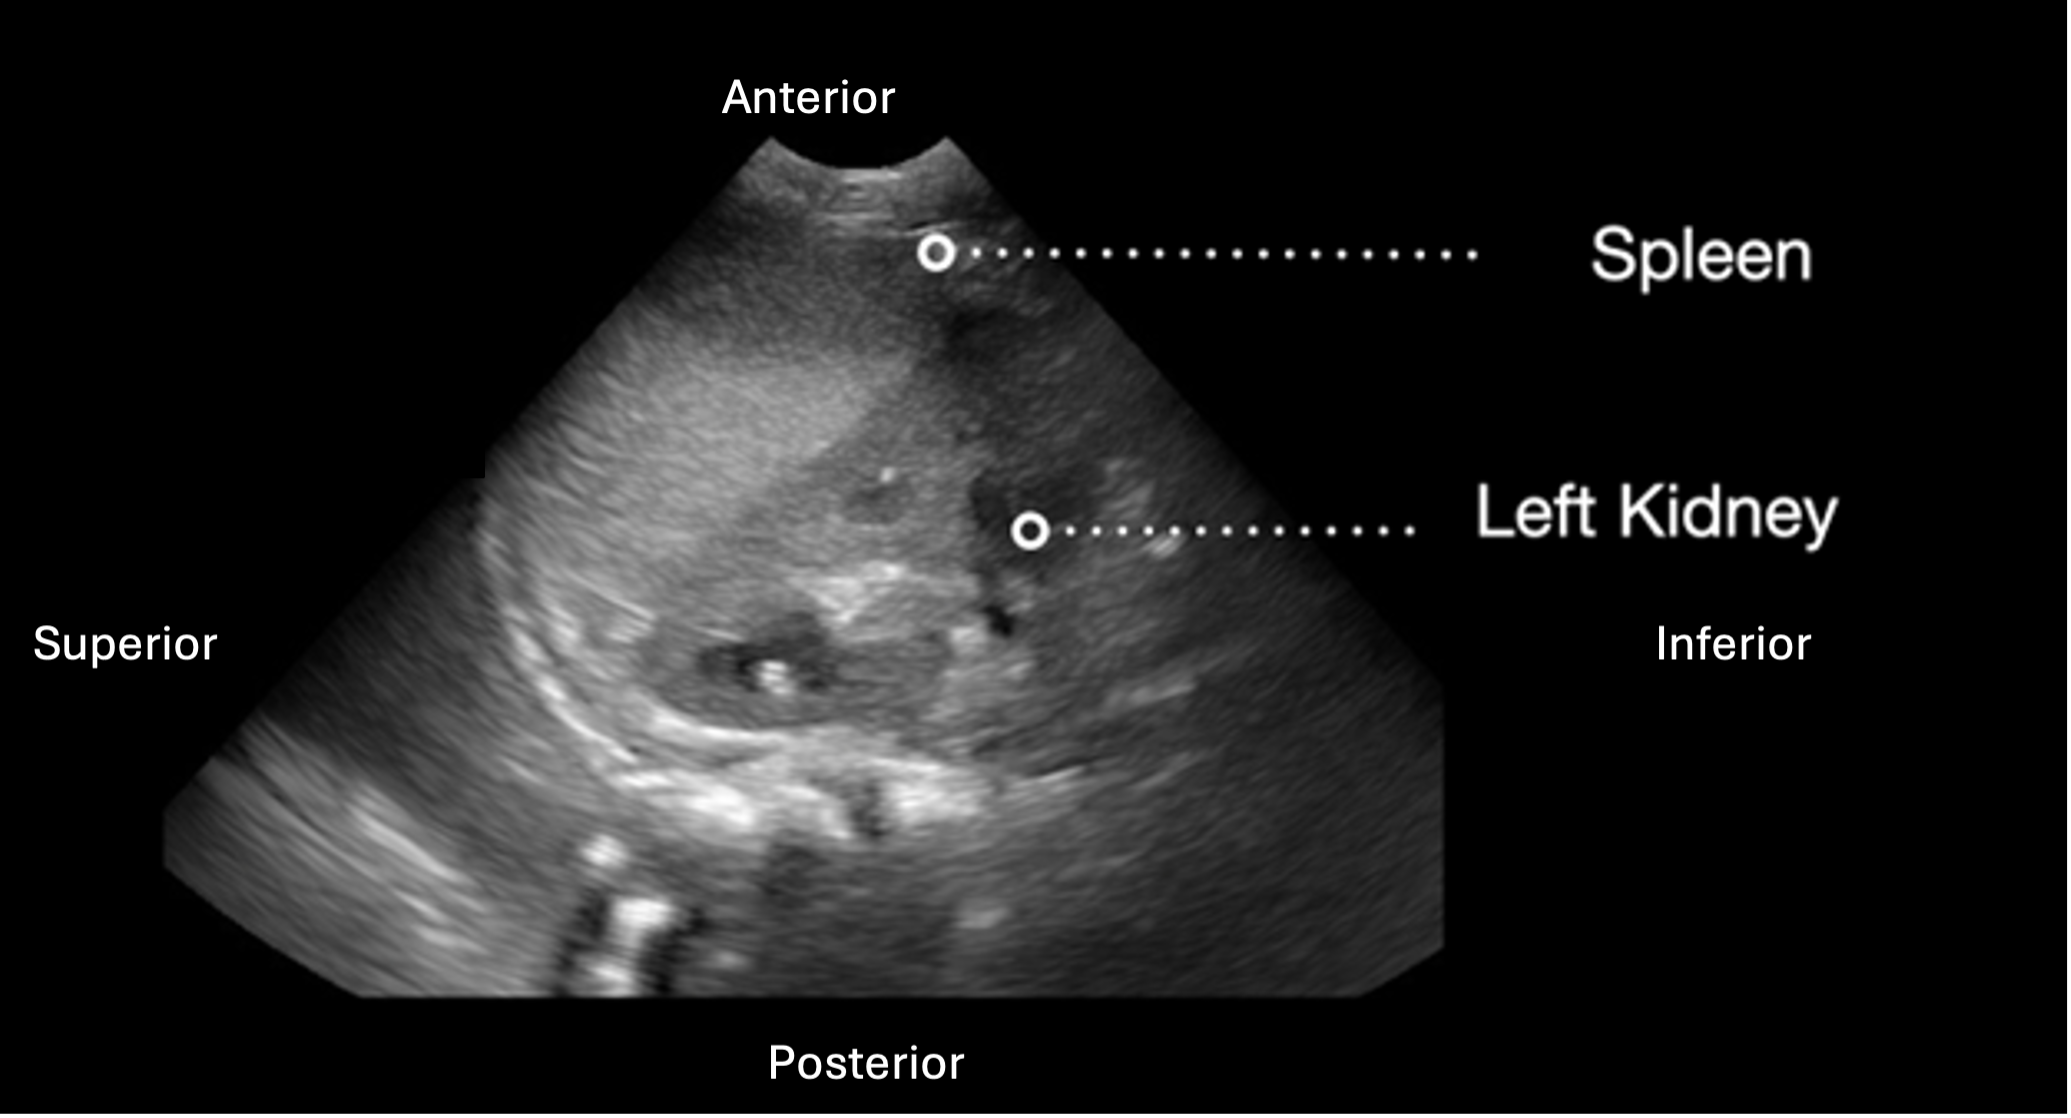

Subcostal Four Chamber

The subxiphoid 4 Chamber view can be used to assess ventricular function, particularly during emergent situations, when access to the other windows is limited.

The left ventricle is seen in the far field with the septal and lateral walls in view. The RV is seen more anteriorly.